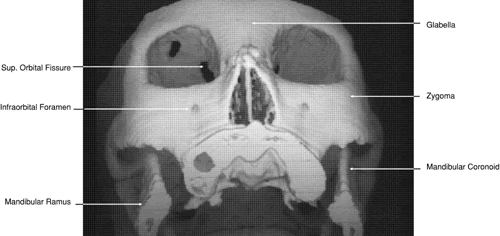

The globe is shown in Figure 12. The orbit and periorbital structures are shown in Figures 13 through 16, and the optic canal is shown in Figures 17 through 26. The cavernous sinus and optic chiasm are shown in Figures 27 and 28, and the posterior visual pathway and cranial nerves are shown in Figures 29 through 33.

Fig. 13. Three-dimensional reconstruction of orbit and infraorbital structures (Water's view).

Fig. 14. Three-dimensional reconstruction of orbit (anterior view).